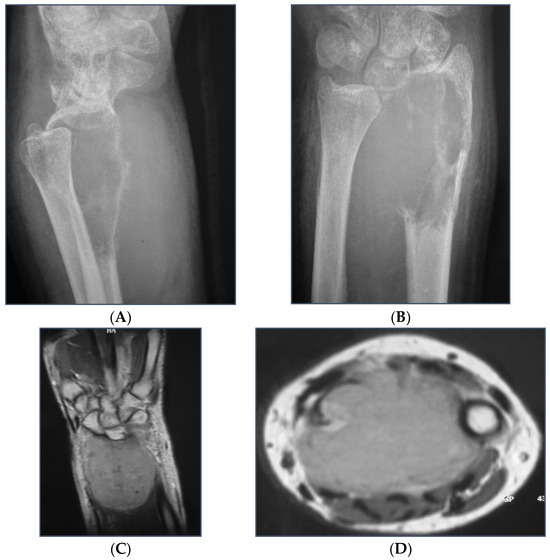

In cases of bone fracture non-union, the surgeon excised scar tissue along with the sequestrum until reaching bleeding bone, following the removal of previously inserted metalwork. For tumor excision cases, the surgeon resected the bone tumor with clear margins or the entire compartment in cases of tumor-induced bone cortex breakage (Figure 1). At this stage, the length of the bone defect was measured to determine the appropriate length of the fibular graft to be harvested (Figure 2). The fibular graft fixation was accomplished using dynamic compression plates (DCPs) or anatomical plates, with a minimum of six cortices engaged on each side using either simple or locking screws (Figure 3). Once the osteosynthesis is completed, it is time to proceed with the vessel anastomosis. First, the peroneal vein is anastomosed to the radial or ulnar vein using 8-0 nylon monofilament sutures. Following this, the surgeon performs the arterial anastomosis using the same type of suture as previously. Simple interrupted stitches are preferred over a continuous suture technique and the anastomosis could be either end to end or end to side using a microscope.

Figure 1.

(A–E): A giant cell tumor of the distal radius that invades the distal articular surface, distal radioulnar joint, and palmar cortex of the radius. The selected treatment involves excision of the distal radius, including the pronator quadratus muscle, the proximal carpal row, and the distal third of the ulna. (F,G): Wrist arthrodesis using an intercalated free pedicled vascularized fibular graft was the treatment of choice.